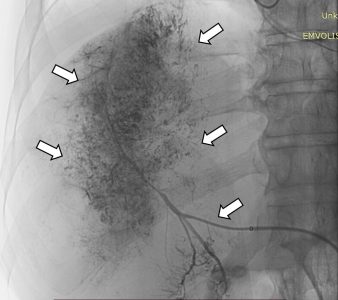

Ακτινολογία

Διαδερμικά κατευθυνόμενη θερμοκατάλυση RF-Ablation ηπατικής μετάστασης από αδενοκαρκίνωμα παχέος εντέρου